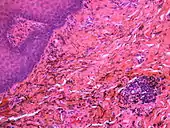

Silver sulfide deposits are found in proximity to small vessels in the oral mucosa

If necessary, the diagnosis can be confirmed histologically by excisional biopsy, which excludes nevi and melanomas.[3]:138 If a biopsy is taken, the histopathologic appearance is:[1]

• Pigmented fragments of metal within connective tissue

• Staining of reticulin fibers with silver salts

• A scattered arrangement of large, dark, solid fragments or a fine, black or dark brown granules

• Large particles may be surrounded by chronically inflamed fibrous tissue

• Smaller particles surrounded by more significant inflammation, which may be granulomatous or a mixture of lymphocytes and plasma cells